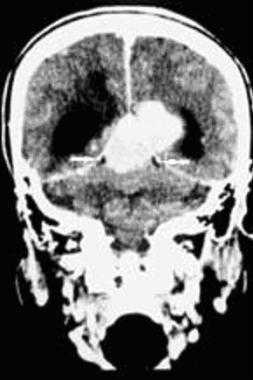

З адняя тенториальная менингиома на корональном КТ-изображении с контрастным усилением. К намету мозжечка прилежит объемное образование повышенной плотности с четкими краями. Визуализируются застой спинно-мозговой жидкости, легкий отек прилежащих тканей, гомогенный характер контрастирования, а также расширение желудочков.

Менингиома теменно-затылочной области: объемная 3D-реконструкция.